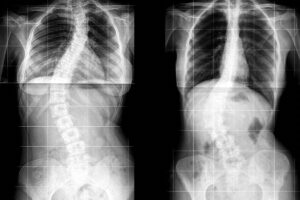

Descubra os tratamentos disponíveis para escoliose em adultos

A escoliose em adultos pode trazer desconfortos significativos e limitar a qualidade de vida, mas existem diversas opções de tratamento para aliviar os sintomas e